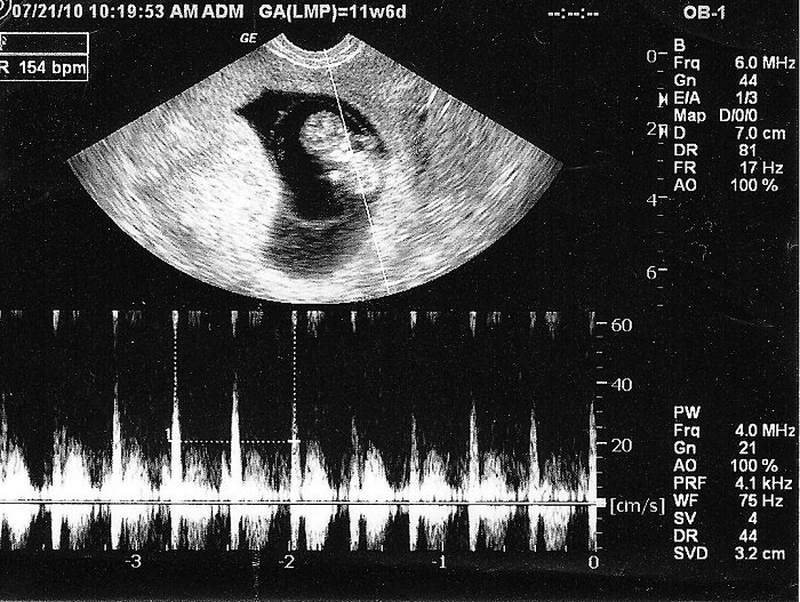

Ban đầu, nhịp tim thai nhi sẽ giao động trong khoảng từ 90 đến 110 nhịp/phút. Ở những tuần tiếp theo thì nhịp tim sẽ tiếp tục tăng tới đỉnh điểm và có thể trong khoảng 140 đến 170 lần/phút. Lúc này khi đi khám thai, các mẹ bắt đầu có những thắc mắc như nhịp tim thai 180 lần/phút là trai hay gái? Vậy liệu dựa vào nhịp tim có thể đoán được giới tính thai nhi hay không?

Vào tuần thứ 16, nhịp tim thai trung bình là khoảng 120 đến 160 lần/phút và có thể tăng lên đến 180 lần/phút khi các bé cử động nhiều. Theo các chuyên gia sản khoa thì giai đoạn chuyển dạ, nhịp tim thai nhi được cho là tốt nhất là từ 110 đến 160 nhịp/phút. Một điều các mẹ bầu cần lưu ý đó là nhịp tim thai nhi cũng giống như nhịp tim của mẹ, khi cử động nhiều đều có thể sẽ thay đổi nhịp tim.

Vậy là bạn đã biết nhịp tim thai nhi như thế nào là nhanh, chậm hay bình thường. Nhiều người đã chuyền tai nhau rằng nhịp tim thai 180 lần phút là trai còn dưới 180 phút lần là gái. Tuy nhiên theo các chuyên gia về sản phụ khoa thì điều này hoàn toàn không chính xác.

Chúng ta không thể chẩn đoán được giới tính của thai nhi bằng việc chỉ dựa theo nhịp tim. Điều này là hoàn toàn không có cơ sở khoa học khi nhịp tim của em bé sẽ thay đổi lên xuống khác nhau sau mỗi lần siêu âm phụ thuộc theo thời kỳ thai sản.